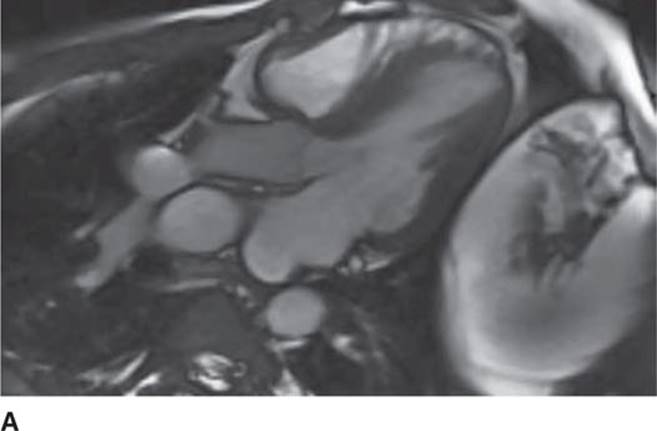

FIGURE 53-7A Cardiac MR with open mitral inflow during diastole. (Used with permission of Dr. Andrew Rivard at University of Mississippi Medical Center, Jackson, MS.)

The 12-lead ECG (see Figure 53-1) should demonstrate LVH and repolarization abnormalities. Incongruence between the ECG and echo findings should lead to definitive evaluation with either cardiac magnetic resonance imaging (CMRI)(Figure 53-7A and 53-7B) or invasive hemodynamic studies in the cath lab. In order to help assess the risk of SCD, HCM patients should also have 24-hour Holter monitoring and a graded exercise test performed at the time of diagnosis to evaluate for the presence of asymptomatic arrhythmias and determine the blood pressure response during exercise.1,4

FIGURE 53-7B Cardiac MR with obstruction of the LVOT during systole due to SAM of the mitral valve. (Used with permission of Dr. Andrew Rivard at University of Mississippi Medical Center, Jackson, MS.)